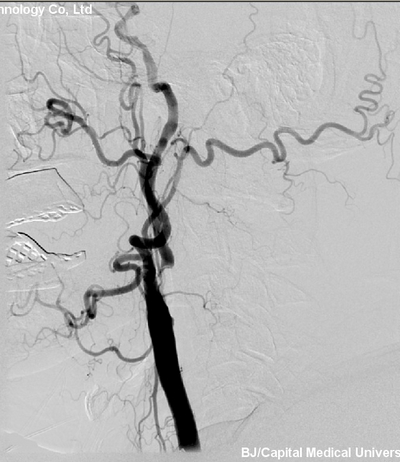

患者入院后行DSA检查,提示双侧颈内动脉重度狭窄。(左侧狭窄99%,右侧狭窄80%)。

患者诊断明确,具备手术指征,2013年4月2日,张勤奕教授于北京安贞医院为其施行了左侧颈动脉内膜剥脱术,手术顺利,患者恢复良好。